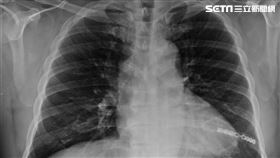

早揪出肺癌「手術+輔助治療」可降復發率

台灣肺癌發生率相當高,更位居台灣癌症死因之首,但肺癌...

肺癌術後接標靶 輔助治療降復發風險

根據衛福部國健署資料 顯示,台灣每年約有1萬3千例新...